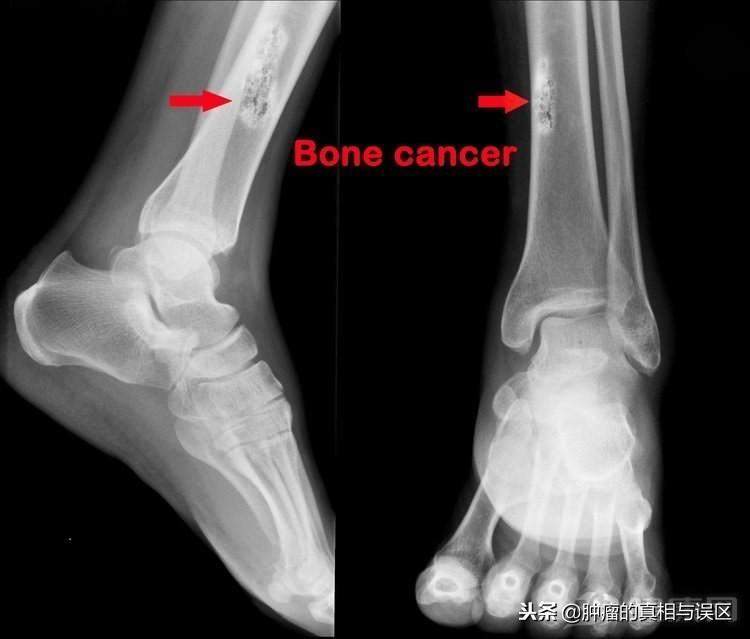

骨癌亦称为恶性骨肿瘤,发生在骨骼或其附属组织的肿瘤,但发展速度快,死亡率高。由于骨癌的早期症状不明显,只有当病情发展到了一定程度,或患者身体局部出现肿胀或疼痛时才会引起注意,因此耽误了很多骨癌患者的最佳治疗时间。那么在骨癌早期会出现哪些症状,导致骨癌的原因又有哪些呢?

早期骨癌很难引起注意,晚期才会出现明显的症状,由于骨癌在任何年龄段的群体都可能会发生,所以当出现以下症状时应该要警惕骨癌的可能了。

当骨癌在早期病情不严重时,最为明显的症状就是疼痛,虽痛感不严重,且间歇性发作,但当病情恶化后,疼痛会逐渐增加,转变为持续性。到了晚期,这种疼痛甚至会导致病人的某些功能出现障碍,发生肌肉萎缩症状。

骨癌一般发生在骨膜下或浅表,会导致骨膨胀变形,并且肢体会感觉到固定性、持续性的疼痛和肿胀。

骨癌早期会出现骨骼变形的情况,因肿瘤挤压影响骨骼的发育及坚固性,下肢骨骼的变化最为明显。

病理性骨折也是骨癌早期的信号,当肿瘤部位受到轻微外力就易发生骨折,还会引起肿胀或剧烈疼痛。